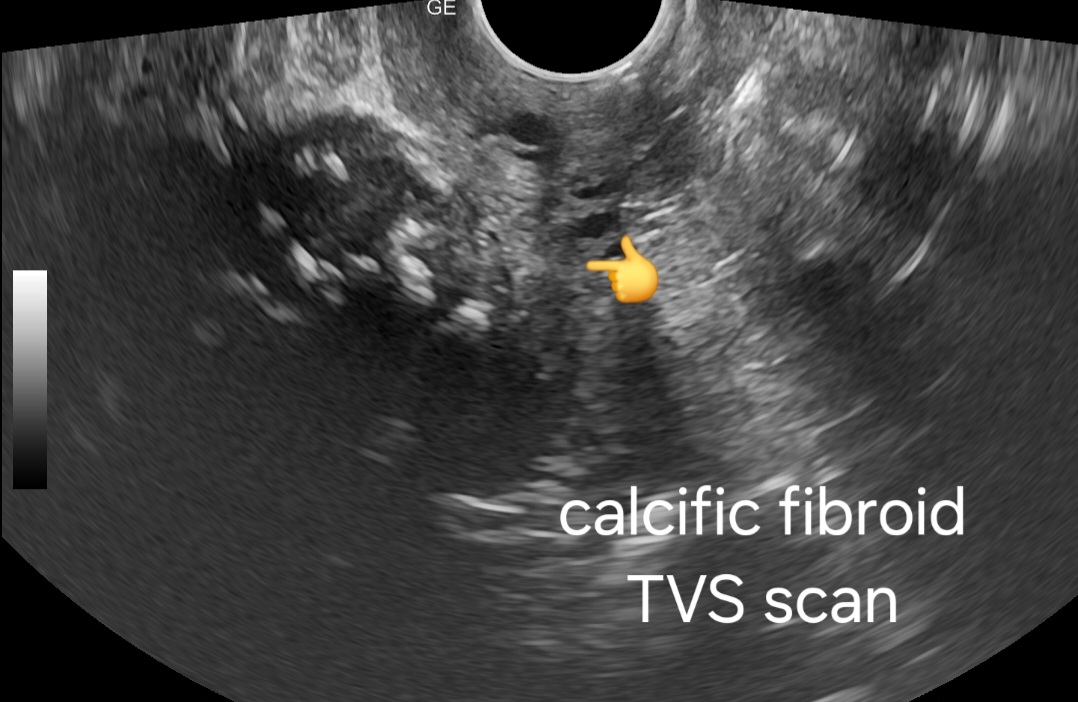

- Transvaginal Scan:

- Higher resolution imaging revealing finer details of fibroid morphology.

- Clearer visualization of calcification patterns within the fibroid.

- May identify any associated complications such as degeneration or necrosis.